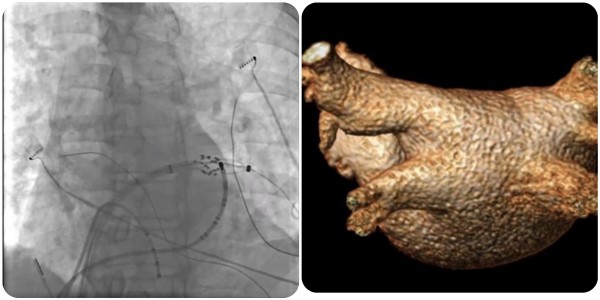

近日,老虎机app (简称老虎机app )心血管内科团队完成广西首批三维标测系统指导下经皮导管脉冲电场消融术(即CardiPulse脉冲电场消融系统上市后广西首批应用),为一名阵发性房颤患者进行了房颤脉冲电场消融治疗,成功帮助患者恢复正常心律。

在夏文豪的指导下,我院心血管内科心律失常介入团队为患者制定了个性化诊疗方案,并联系介入导管中心、重症医学科、心胸外科、手术麻醉中心做好应急预案,为手术全程保驾护航。手术仅2小时,消融过程中患者心律转为正常,肺静脉即刻隔离,术后恢复良好,目前已康复出院。

脉冲电场消融(Pulsed Field Ablation,PFA)利用短时程、高电压的多个电脉冲释放消融能量,可在细胞膜上产生不可逆的纳米级微孔,导致细胞死亡,可用于房颤导管消融,实现肺静脉隔离。